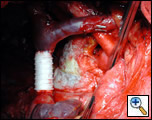

| Figure 3: Coverage of the parenchymal resection line of the lung |

Effective sealing of established air leaks with fleece-bound sealant was proven in a multi-center study of standard lobectomy with significant reduction of duration and magnitude of postoperative air leaks. However, no benefit from prophylactic use was demonstrated, limiting the application of fleece-bound sealant to the treatment of intra-operatively detected air leaks only [3]. This method seems to be very effective in emphysematous disease, where other forms of treatment are difficult and eventually impossible [Figure 3].